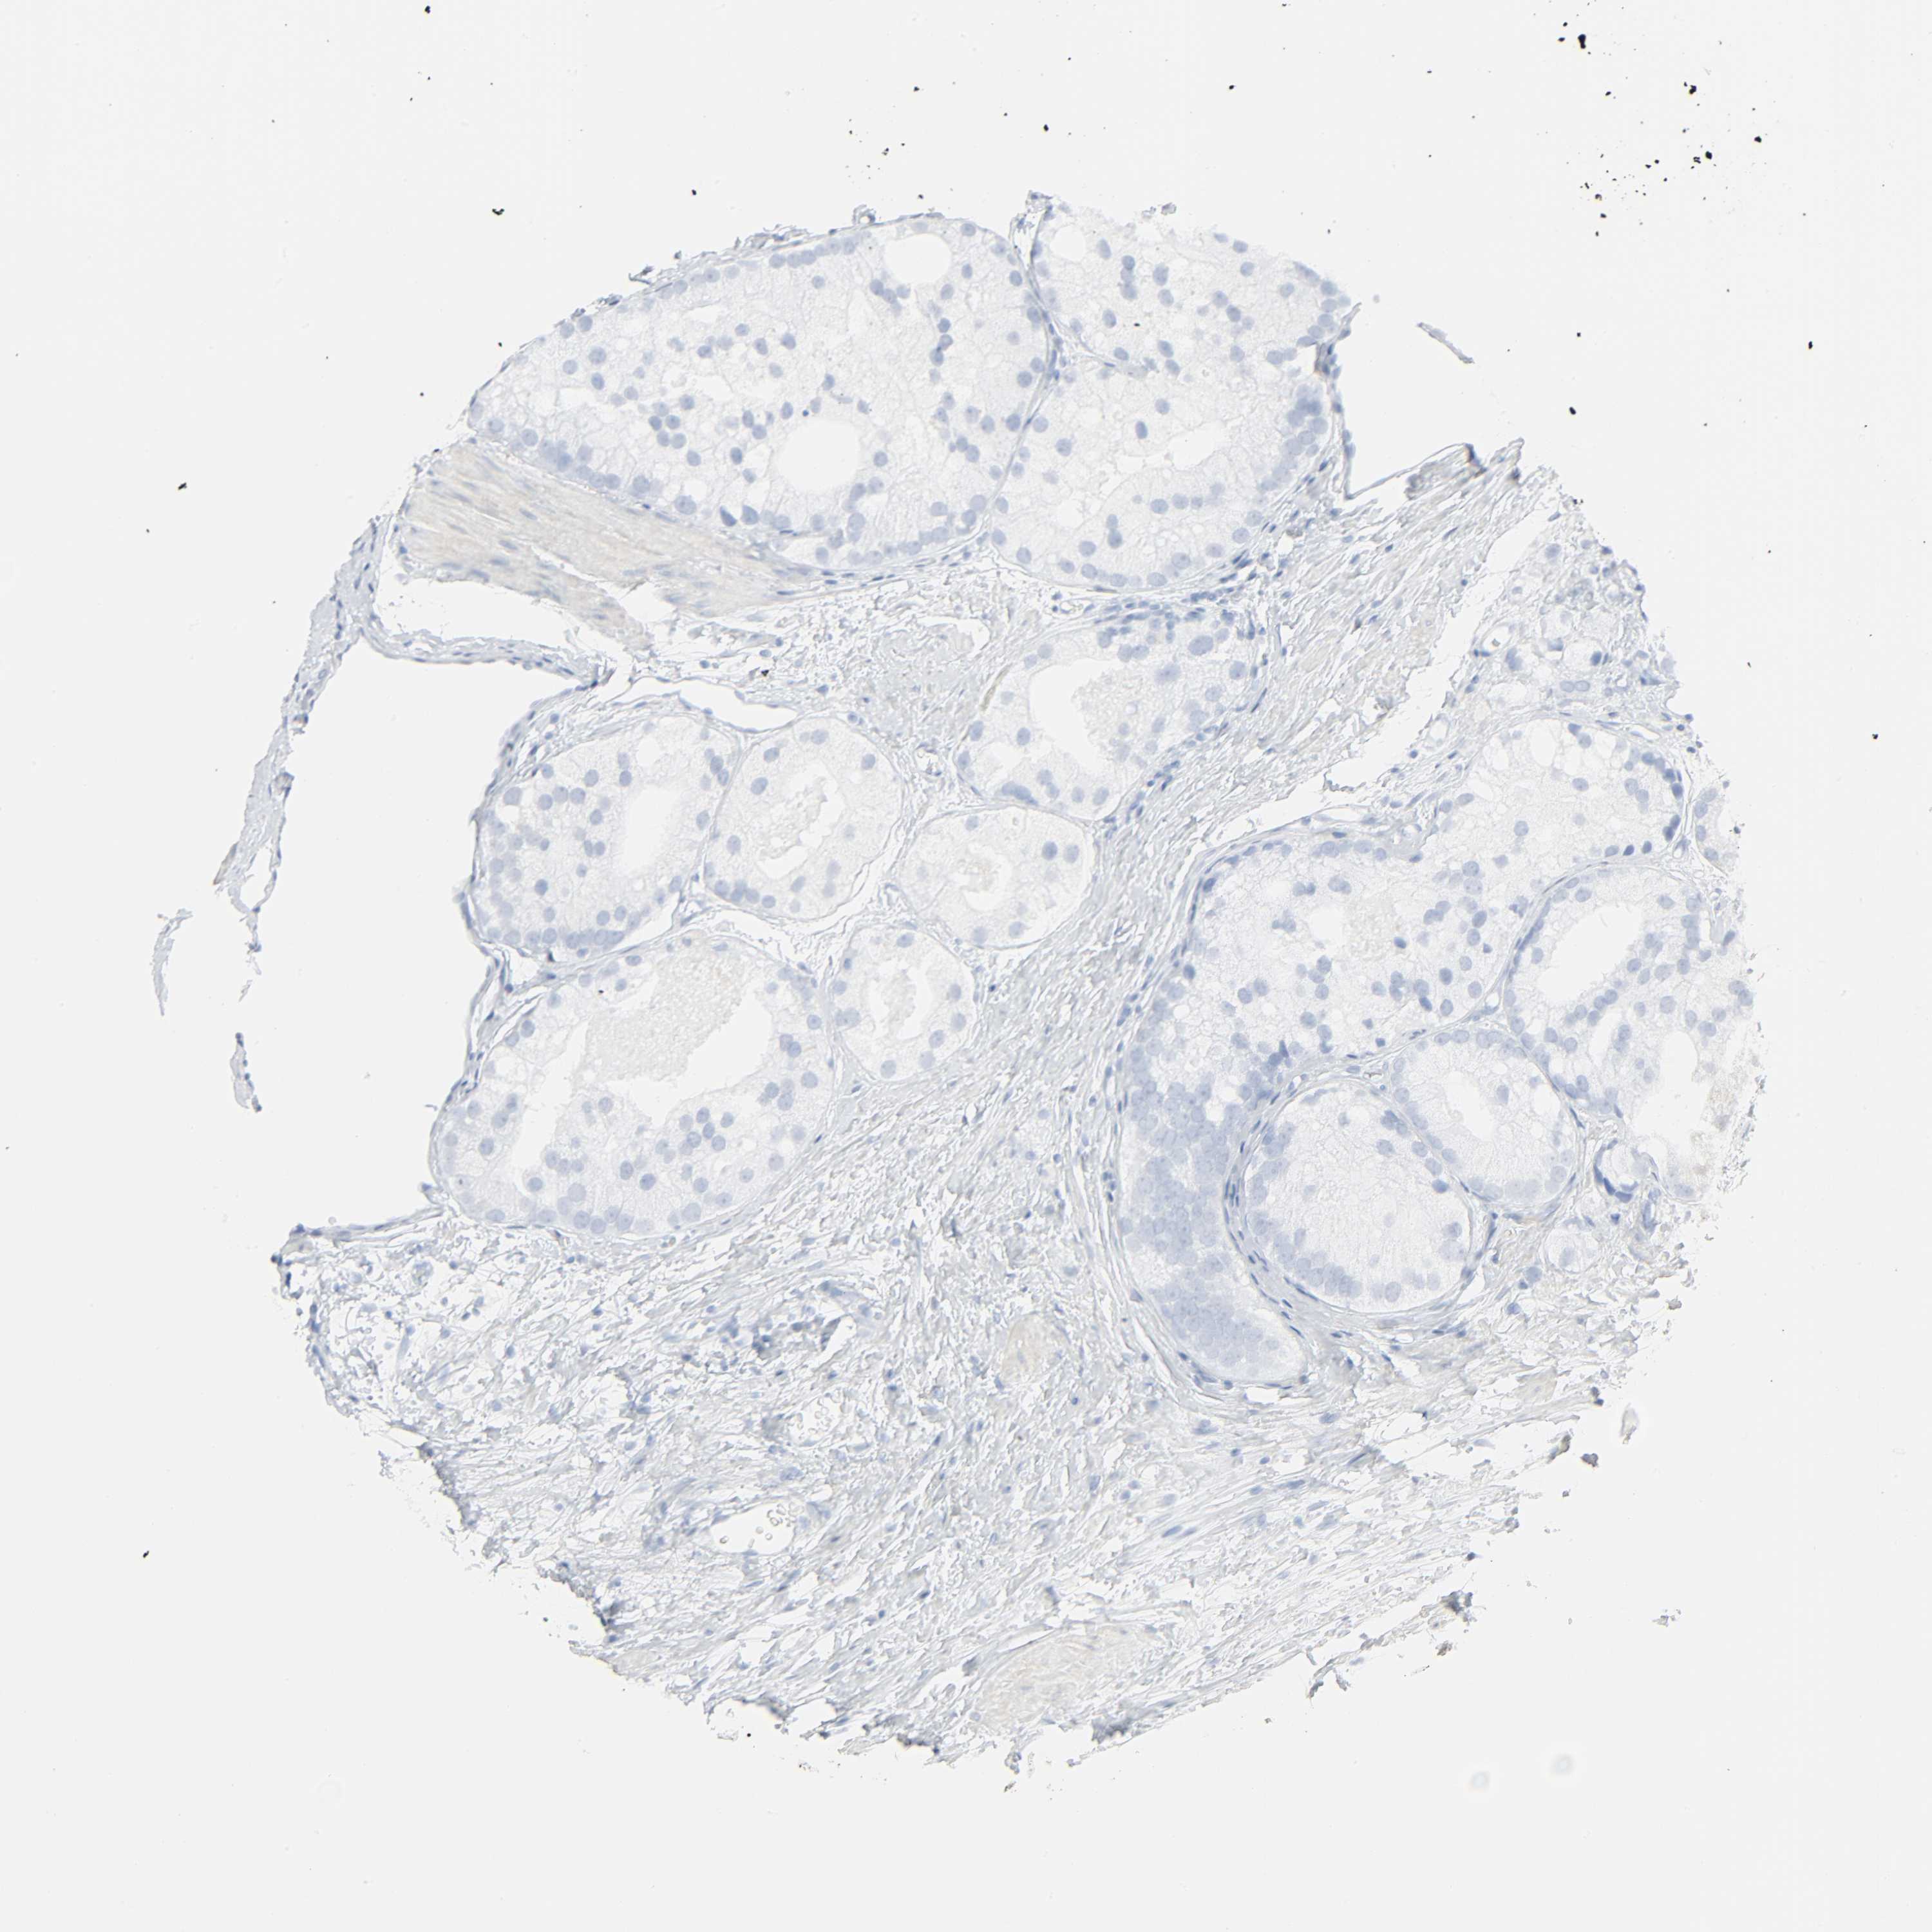

PROSTATE CANCER - Protein expressioni

A mouse-over function shows sample information and annotation data. Click on an image to view it in a full screen mode. Samples can be filtered based on level of antibody staining by selecting one or several of the following categories: high, medium, low and not detected. The assay and annotation is described here.

Antibody stainingi

Antibody staining in the annotated cell types in the current human tissue is reported as not detected, low, medium, or high, based on conventional immunohistochemistry profiling in selected tissues. This score is based on the combination of the staining intensity and fraction of stained cells.

Each image is clickable and will lead to virtual microscopy that enables deeper exploration of all samples and also displays staining intensity scores, fraction scores and subcellular localization as well as patient and tissue information for each sample.

Antibody CAB004540

Adenocarcinoma, Medium grade

Adenocarcinoma, High grade

Adenocarcinoma, Low grade